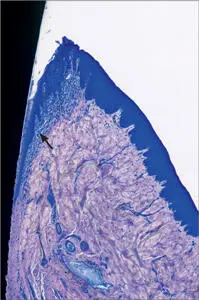

Fig 8 Higher magnification Coronal portion of the supracrestal periimplant - фото 12

Fig 8 Higher magnification. Coronal portion of the supracrestal peri-implant soft tissues. The oral and sulcular epithelium are clearly visible. The collagen fibers located apically to the junctional epithelium run parallel to the implant surface. A more diffuse inflammatory infiltrate (arrow) is located immediately adjacent the junctional and sulcular epithelium.